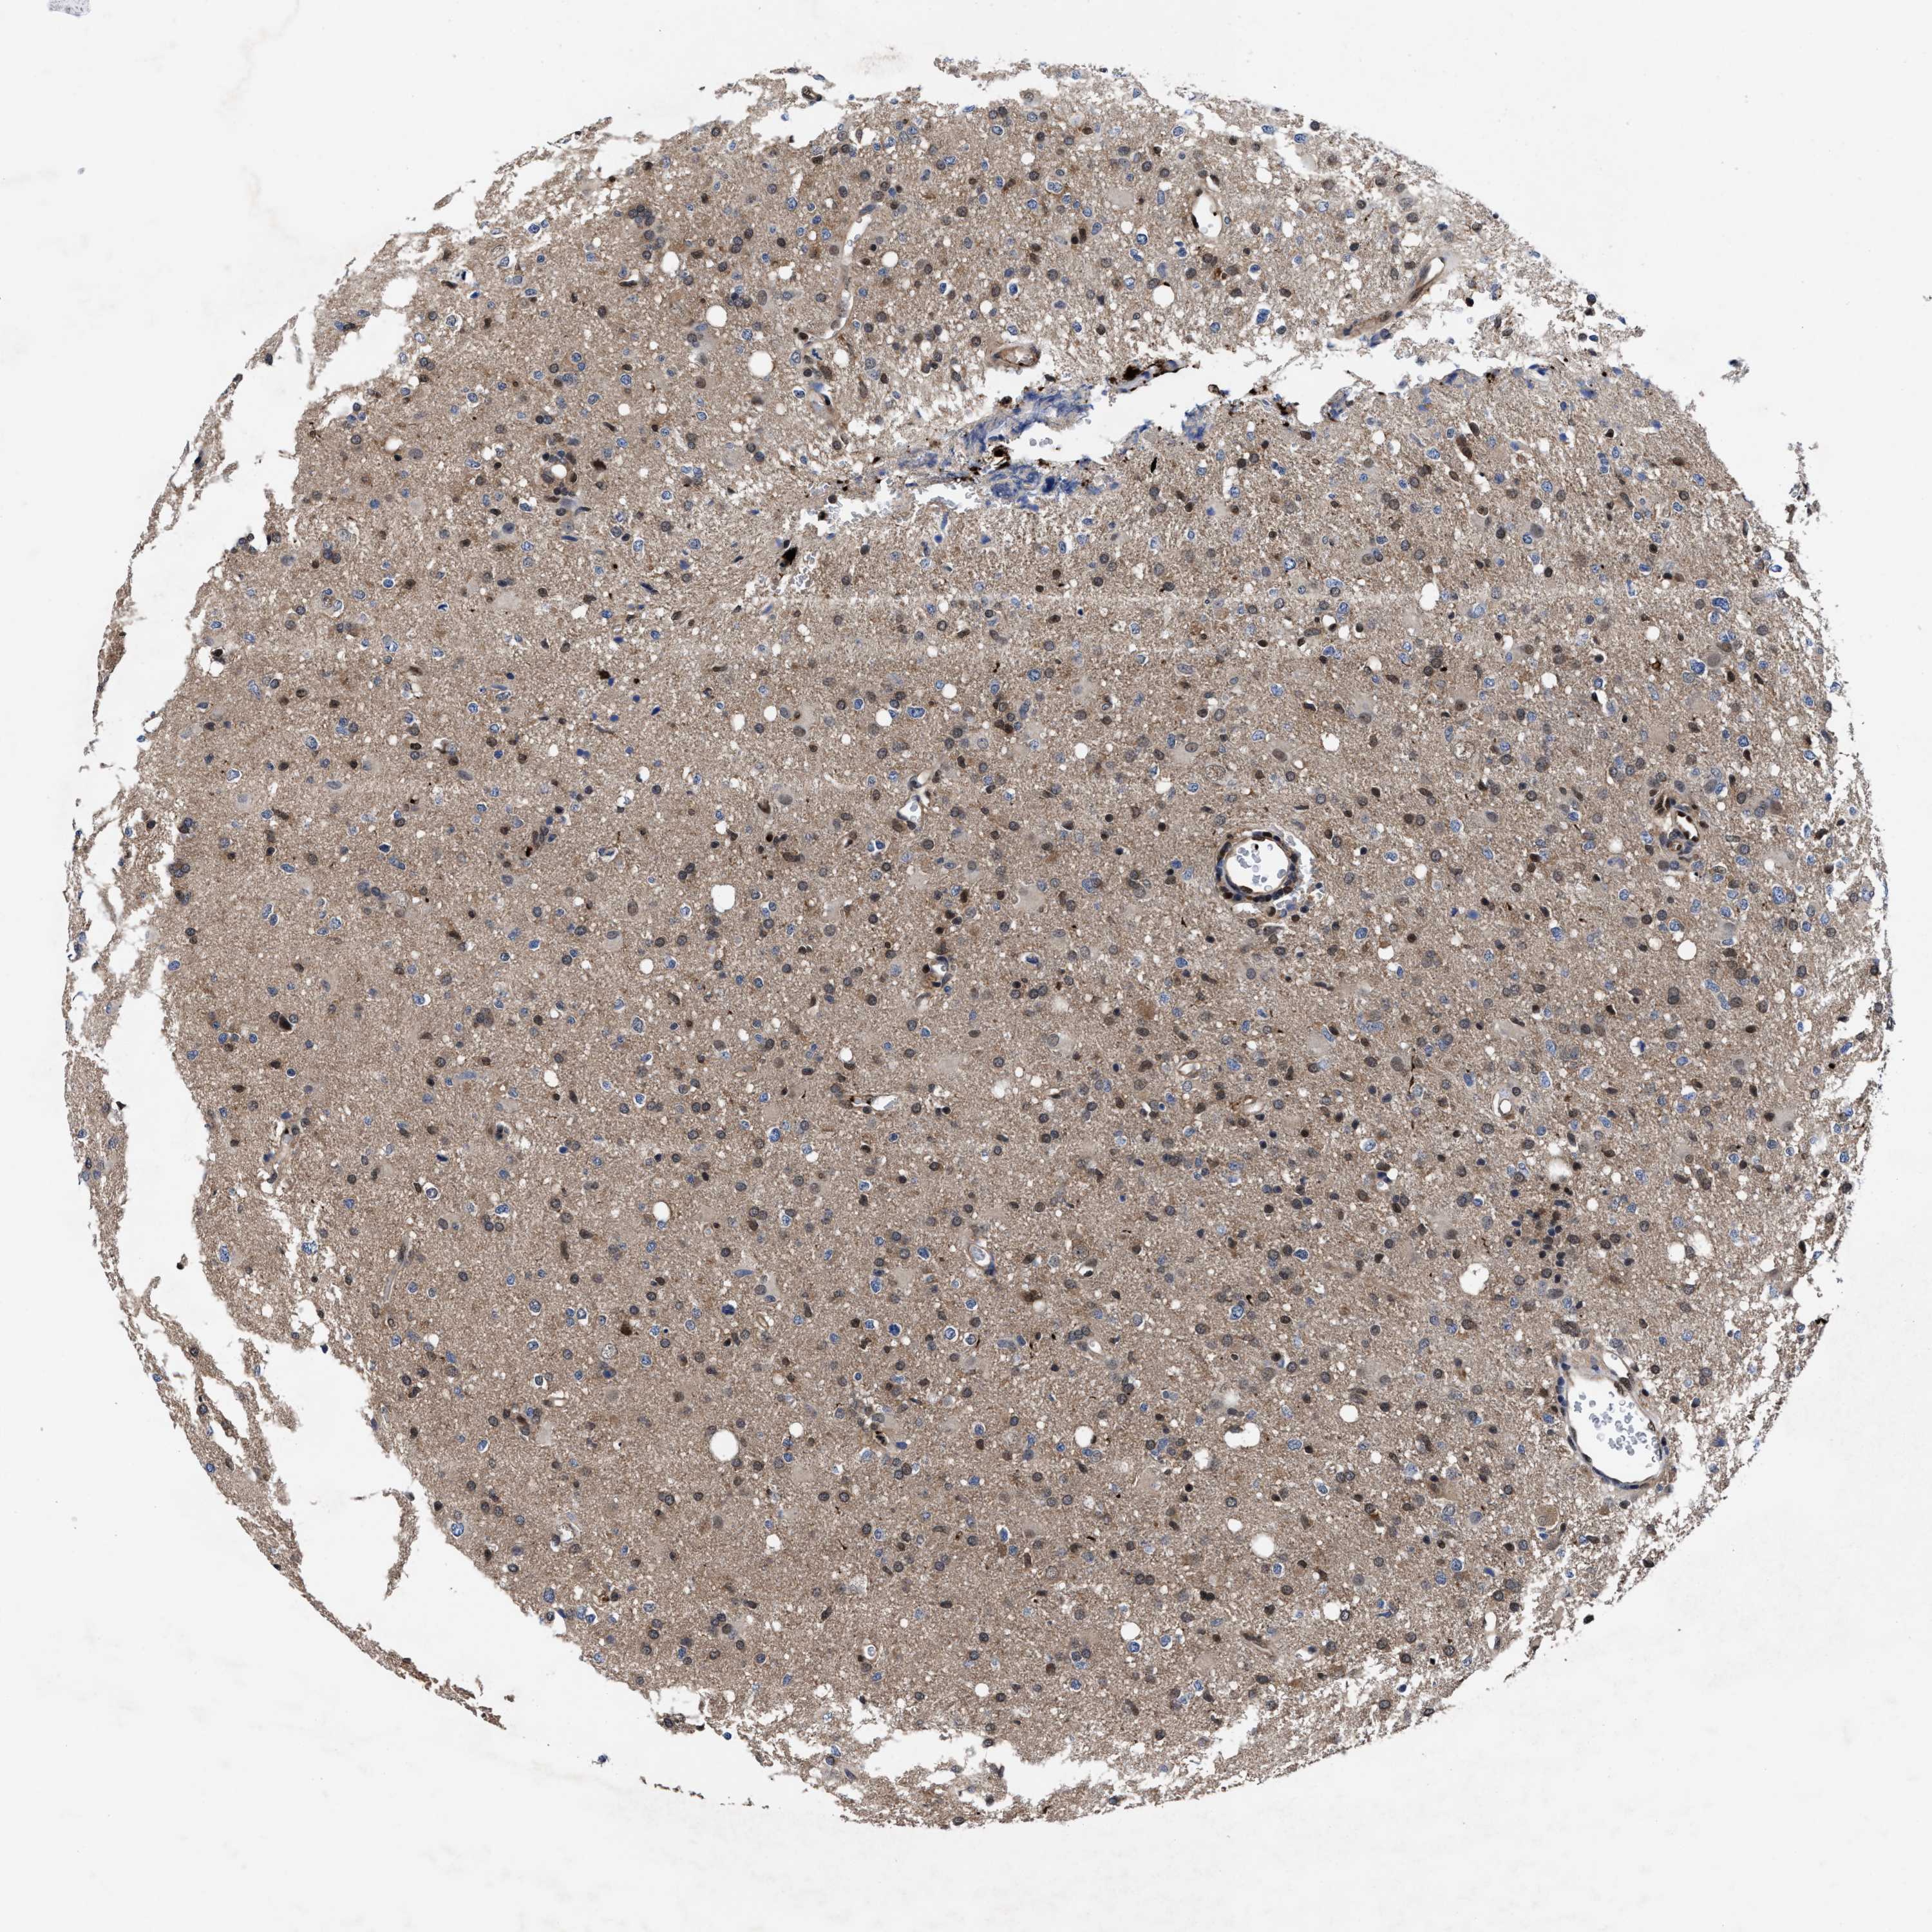

GLIOMA - Protein expressioni

A mouse-over function shows sample information and annotation data. Click on an image to view it in a full screen mode. Samples can be filtered based on level of antibody staining by selecting one or several of the following categories: high, medium, low and not detected. The assay and annotation is described here.

Note that samples used for immunohistochemistry by the Human Protein Atlas do not correspond to samples in the TCGA dataset.

Antibody stainingi

Antibody staining in the annotated cell types in the current human tissue is reported as not detected, low, medium, or high, based on conventional immunohistochemistry profiling in selected tissues. This score is based on the combination of the staining intensity and fraction of stained cells.

Each image is clickable and will lead to virtual microscopy that enables deeper exploration of all samples and also displays staining intensity scores, fraction scores and subcellular localization as well as patient and tissue information for each sample.

HPA022434

HPA022953

HPA022959

HPA028758

CAB007783

Glioma, malignant, High grade

Glioma, malignant, Low grade

Glioblastoma, NOS